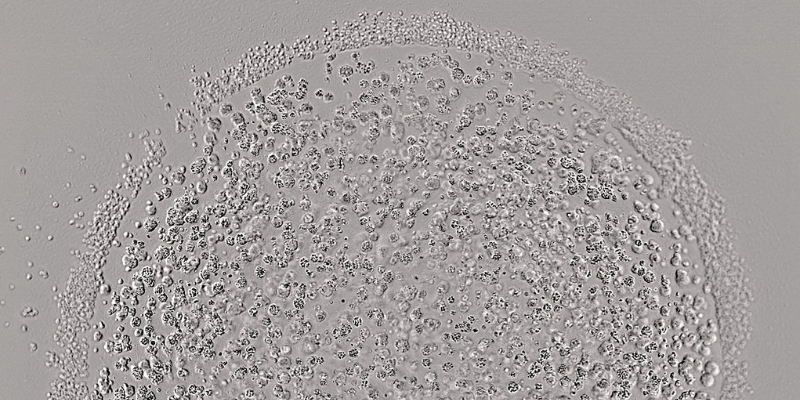

Cancer drug resistance causes and categories identified

Researchers have mapped the genetic landscape of cancer drug resistance, uncovering that DNA changes can be grouped into four main categories and highlighting possible new therapeutic targets.

All cancer mutations that cause drug resistance fall into one of four categories. New research has detailed each type, helping to uncover targets for drug development and identify potential effective second-line therapies.